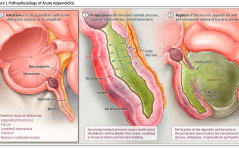

Für Sie kommentiert

Unerklärte Sterilität: hoffnungsvoll / Topische Östrogene bei älteren Frauen / Inzidentelle Salpingovarektomie / BRCA 1 / 2: Pathogene Varianten / Akute Appendizitis: Antibiotikatherapie PDF Dokument